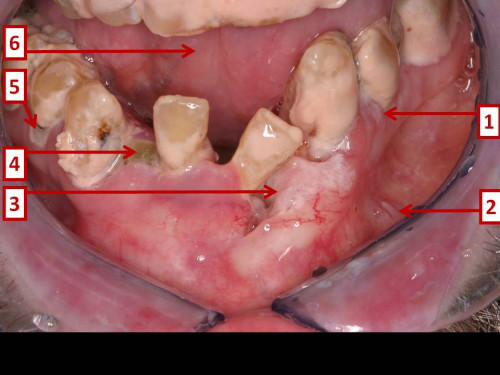

Mundraum-Inspektion eines Alkoholikers

53 Jahre alter Alkoholiker. Er wird von einem Zahnarztkollegen an die Mund-, Zahn-, und Kieferchirurgie überwiesen. Er selbst kann nicht genau sagen, dass ihm jemals etwas Besonderes in seinem Mund aufgefallen wäre.

Welche Aussage zu den gezeigten Veränderungen im Mund trifft zu?

- A1 ist wahrscheinlich abwischbar.

- B2 ist wahrscheinlich abwischbar.

- C3 ist wahrscheinlich abwischbar.

- D3 respektiert die Mittellinie nicht.

- E5 zeigt eine andere Veränderung als 1.

Makroskopie - Bild 2